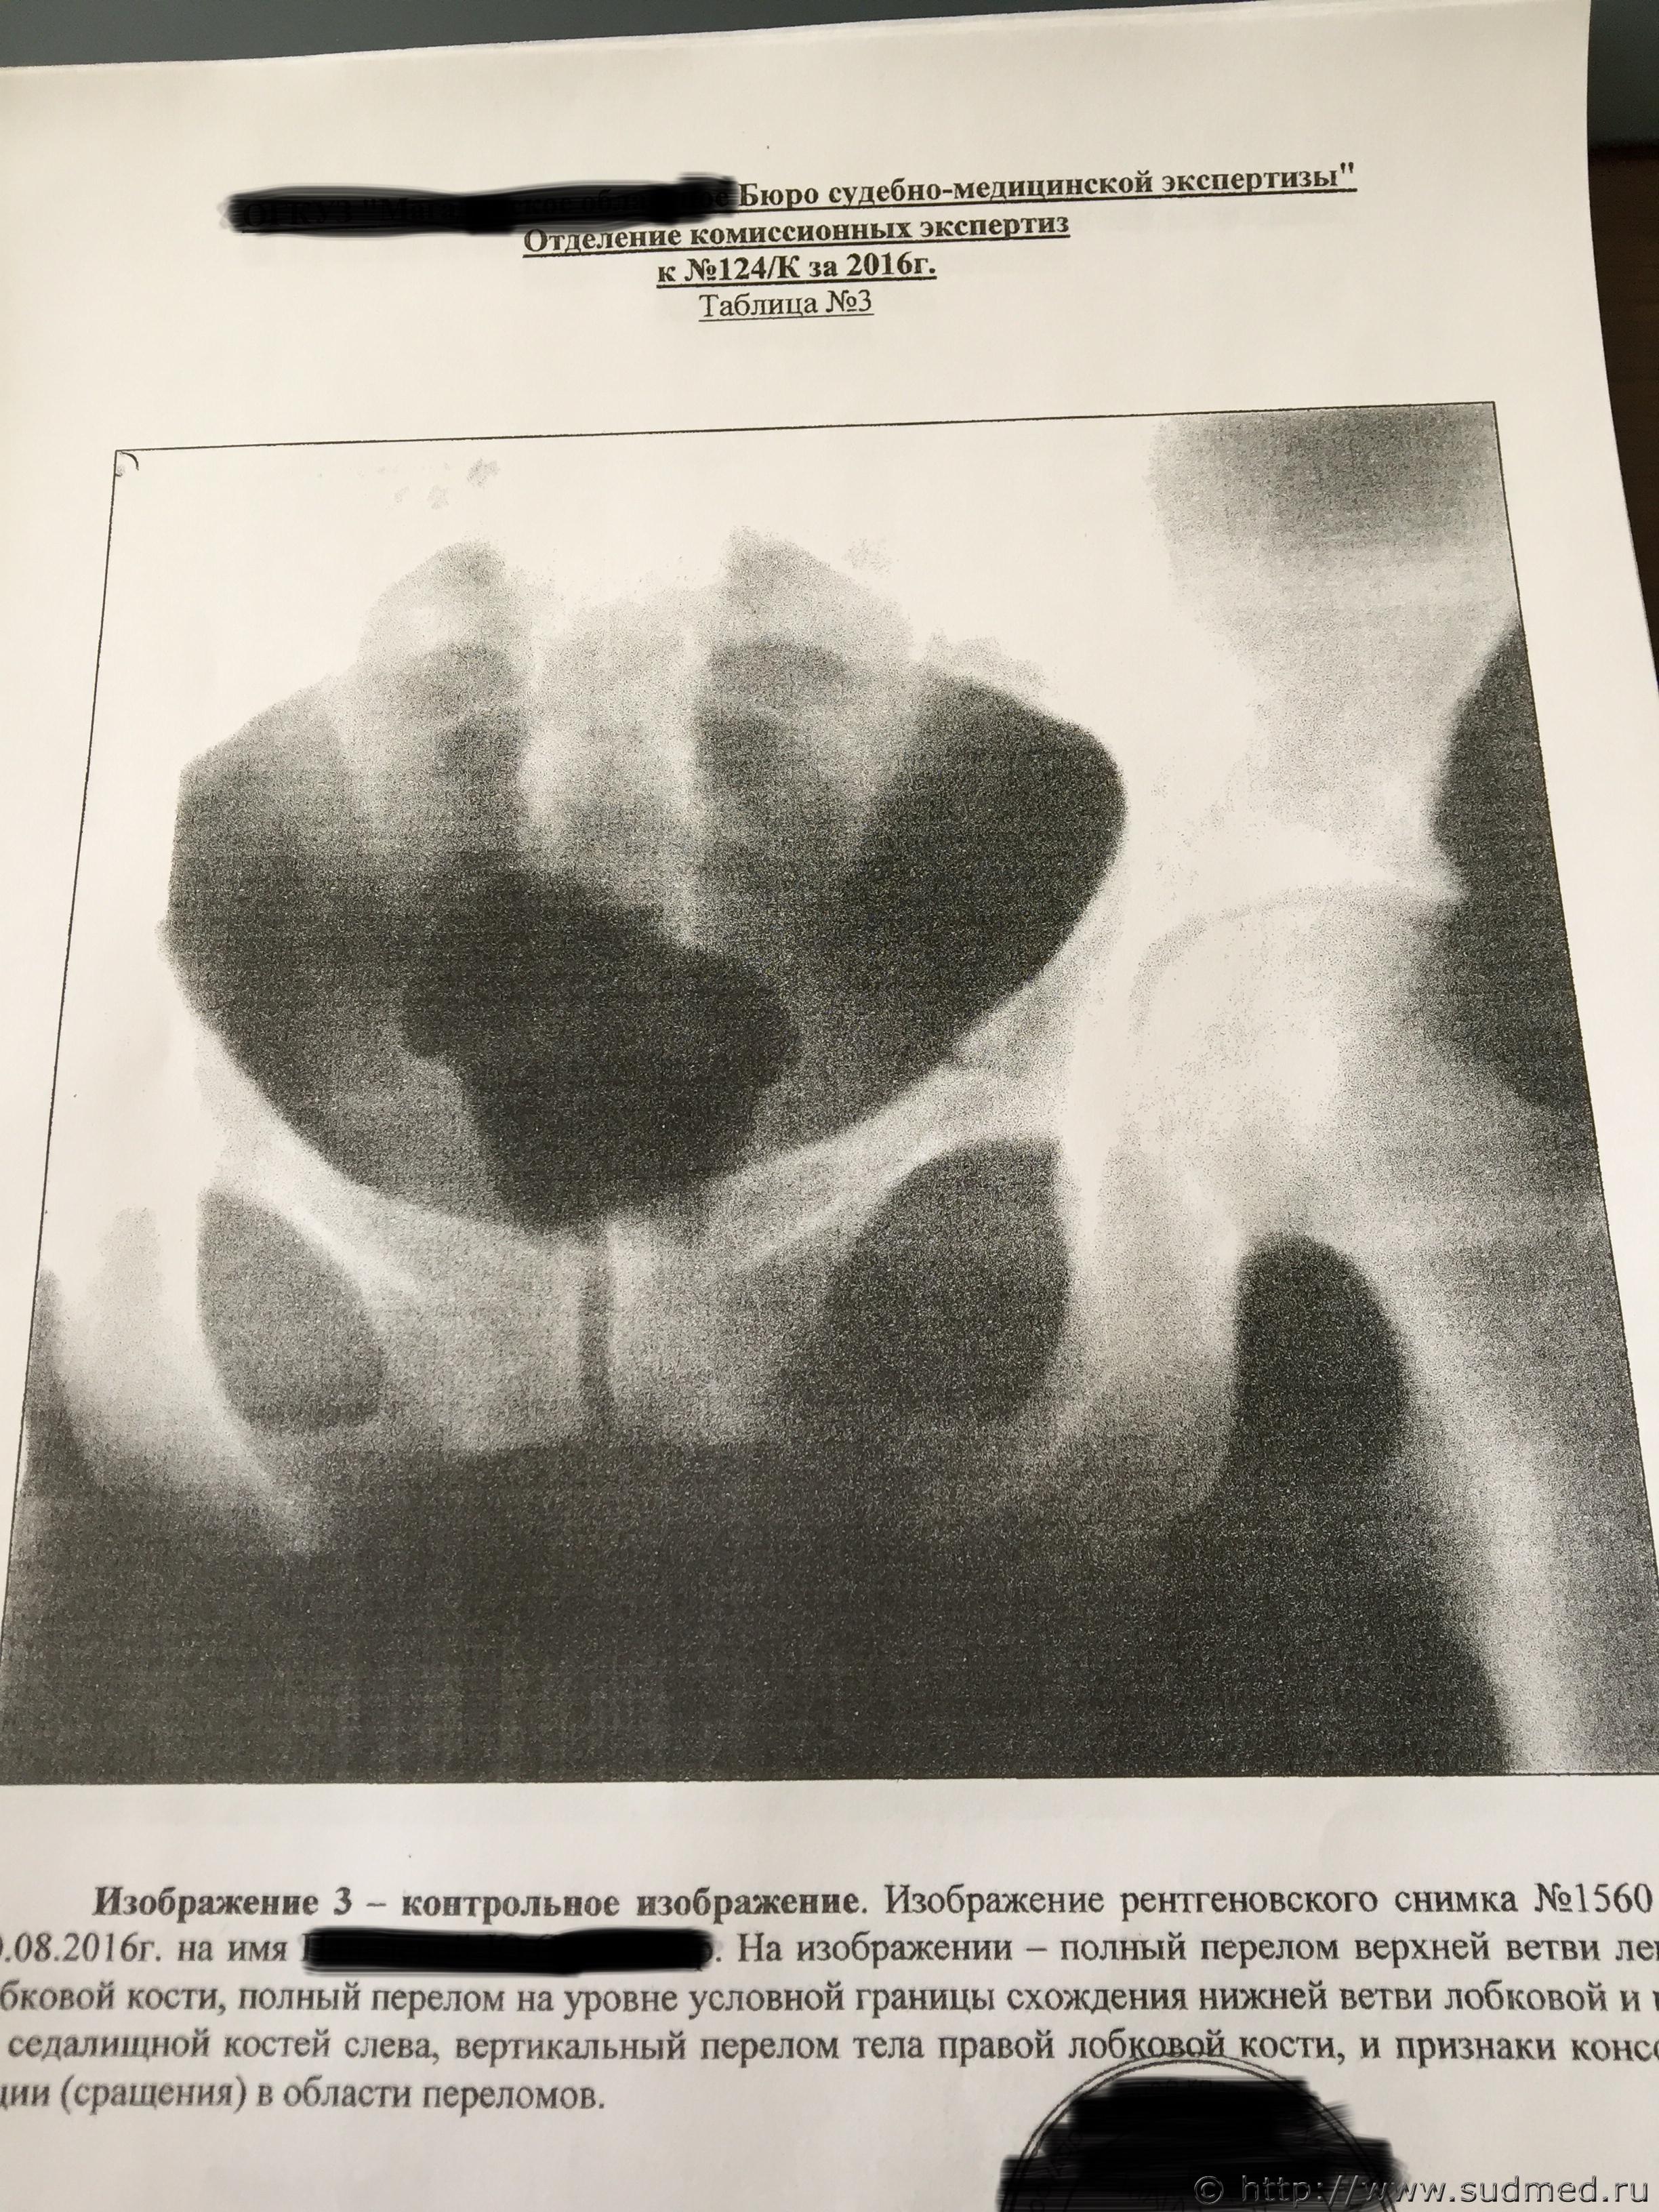

По вашей рекомендации я написал ходатайство о проведении повторной комиссионной экспертизы и сам в ней участвовал, так как разобрался с вашей помощью во всех деталях, практический, все включая следователя были уверены, что вред квалифицируют, как средней тяжести, но по результатам повторной экспертизы, каким то странным образом эксперты нашли еще один третий перелом правой лобковой кости, в результате чего вред здоровью стал действительно Тяжким.

Посмотрите, пожалуйста, третье заключение экспертизы, а то закрадывается сомнения о том, что смотрели три рентгенолага и установили три разных диагноза, и правильно ли они определили третий перелом.

Отправляю заключение комиссионной экспертизы и рентгенные снимки сразу после происшествия и по истечению двух месяце.

снимки сразу после аварии, через 2 месяца и через 3 месяца

Не могу разглядеть перелом правой лобковой кости, и, соответственно, 6.1.23.

На рентгенограммах хорошо видны переломы: правой лонной и правой седалищной костей, левой лонной кости. Перелома левой седалищной кости нет. "Условная граница" левой лонной и левой седалищной костей, на самом деле, находится на некотором расстоянии от места перелома левой лонной кости. Т.е. ссылка экспертов на прохождение линии перелома по этой условной границе представляется изрядно притянутой и, в любом случае, это непосредственно не свидетельствует о наличии перелома левой седалищной кости. Для оценки этой травмы как тяжкий вред нужен перелом типа "бабочки" всех четырех костей: правой лонной (он есть), правой седалищной (есть), левой лонной (есть), левой седалищной (нет!).

Убежден, что за такой перелом тяжкий вред давать неправильно. Это - вред здоровью средней тяжести (по п.7.1 вышеуказанного документа).

Путаница в сторонах переломов: на одном снимке противоположная сторона переломов верхней ветви лонной и ветви седалищной кости обозначена R, на остальных - L. Это может быть принципиальным. В остальном согласен: 6.1.23. отсутствует.